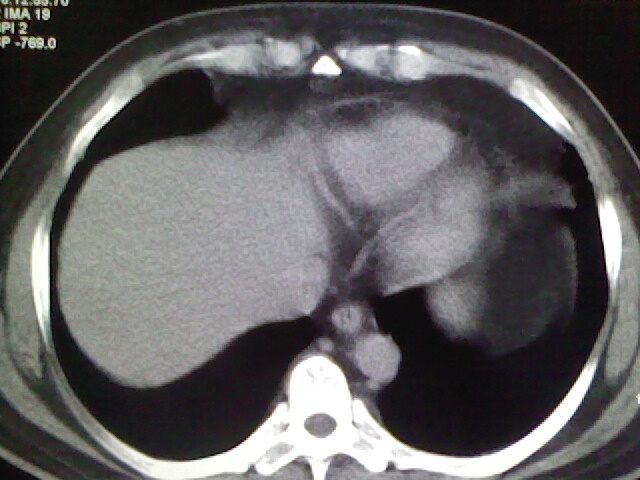

标题: CT17932:临床怀疑肺栓塞

男,34岁,自觉右侧胸痹,胸闷3天余

未见明显异常。图像上看此患者比较肥胖,建议查下心超

肺部大致正常,有可能给心脏需作个检查。

右侧肺动脉似见密度稍低影,请在机器的薄层上再看看有没有充盈缺损。